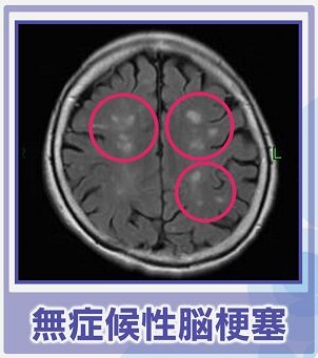

脳梗塞などの疾患

脳梗塞になると、血圧が上昇する傾向があるそうです。これは、脳への血流を維持しようとする体の反応によるものです。しかし、血圧が過度に上昇すると、脳出血のリスクが高まるため、慎重な管理が必要です。